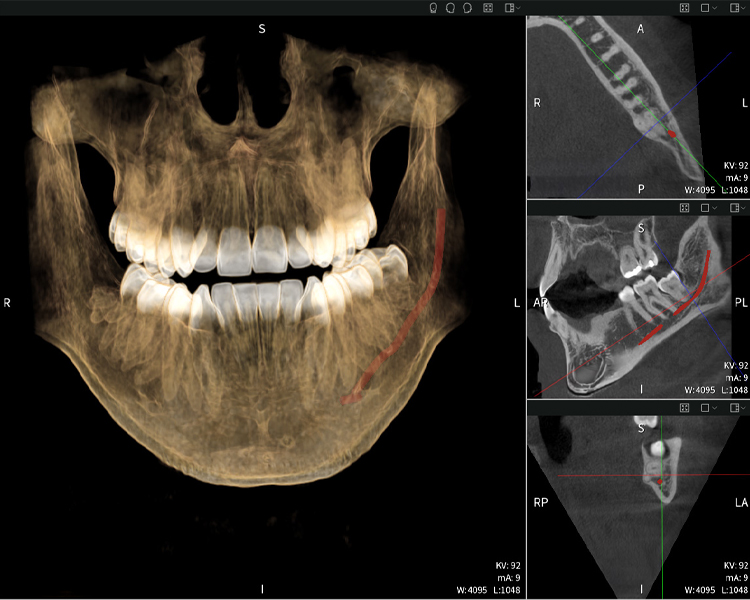

Figure b: Imaging results of Seethrough Max, in front of a black background.

Figure b

Figures b–d show various views of a 3D reconstruction of the mandible, providing a comprehensive overview of the mandibular anatomy, the position of the nerves in relation to the teeth, and allowing assessment of tooth symmetry and alignment.